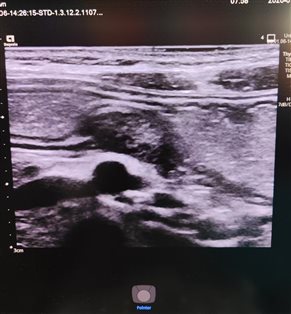

患儿男性,6岁,因阵发性腹部疼痛来诊。患儿口服300毫升胃肠超声造影剂后,于胃窦部小弯侧发现一实性团块,病变起自于黏膜下层,累及固有肌层。超声诊断考虑异位胰腺。

1. 形态与大小:多为圆形、椭圆形的实性结节,大小一般在数毫米到数厘米不等,边界相对清晰。

2. 内部回声:回声强度和正常胰腺组织类似,多为中等回声,分布比较均匀;如果异位胰腺组织内出现囊性变、钙化或脂肪浸润,回声会变得不均匀。

3. 特征性表现:部分病灶可出现 “导管征”,即超声下能看到一个细小的无回声管状结构,这是异位胰腺内的胰管,是相对有辨识度的征象。

与周围组织的关系:病灶通常紧贴消化道黏膜层或黏膜下层,和周围组织没有明显粘连,加压超声探头时,结节形态变化不明显。